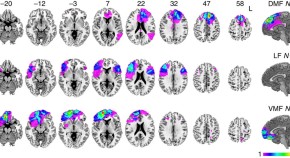

In value-based decisions, the longer one fixates on an option, the more likely one is to choose it. Here, the authors compare the performance of people with focal frontal lobe damage in a simple choice task and show that damage to the dorsomedial PFC leads to exaggerated fixation-related value updating.